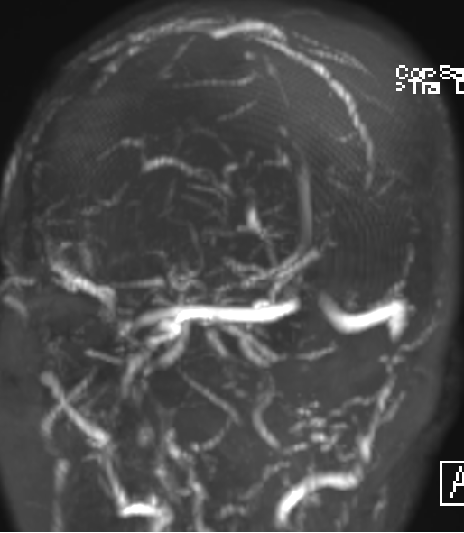

2015-1-30 DSA

脑积水 OR 颅内静脉血栓?